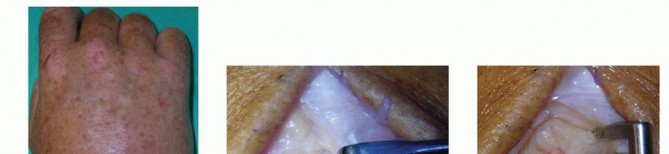

Arthroscopic Drainage of the Wrist Joint

Wrist arthroscopy has revolutionized the management of radiocarpal and midcarpal septic arthritis. It allows for comprehensive visualization, targeted debridement of loculations, and high-volume irrigation with significantly less surgical trauma than an open dorsal arthrotomy.

1. Setup and Portals: The hand is placed in sterile traction using a specialized wrist tower, with 10-15 lbs of distraction applied via finger traps on the index and middle fingers. Standard radiocarpal portals (3-4 and 6R) are established.

2. Initial Evaluation: A 2.7-mm or 1.9-mm arthroscope is introduced through the 3-4 portal. It is critical to perform the initial diagnostic sweep using a "dry" technique or with very low fluid pressure. High-pressure fluid influx can cause massive extravasation of contaminated fluid into the surrounding soft tissues, potentially creating secondary abscesses or compartment syndrome.

Image

1. Debridement and Lavage: Once the portals are secure and outflow is established (often through the 6R portal or a dedicated ulnar outflow portal), an arthroscopic shaver is introduced. Fibrinous debris, hyperplastic infected synovium, and loculations are systematically debrided. The radiocarpal space, including the volar recesses and the prestyloid recess, must be visualized and cleared.

1. Midcarpal Assessment: Following radiocarpal debridement, the midcarpal joint must be assessed via the midcarpal radial (MCR) and midcarpal ulnar (MCU) portals. Septic arthritis frequently involves both joint spaces, and failure to debride the midcarpal joint is a common cause of treatment failure.